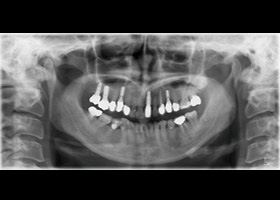

治療前全口X光片、口內正面照片。

假牙完成X光片。